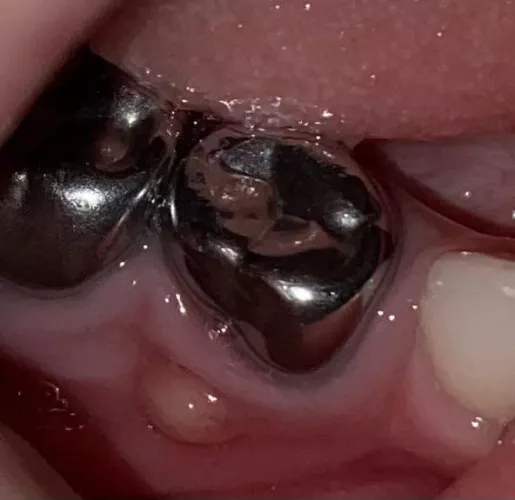

Infected operculum - pericoronitis. An infected flap of gums that falls across the molar. It hurts like hell. On antibiotics. I apologize for nothing.